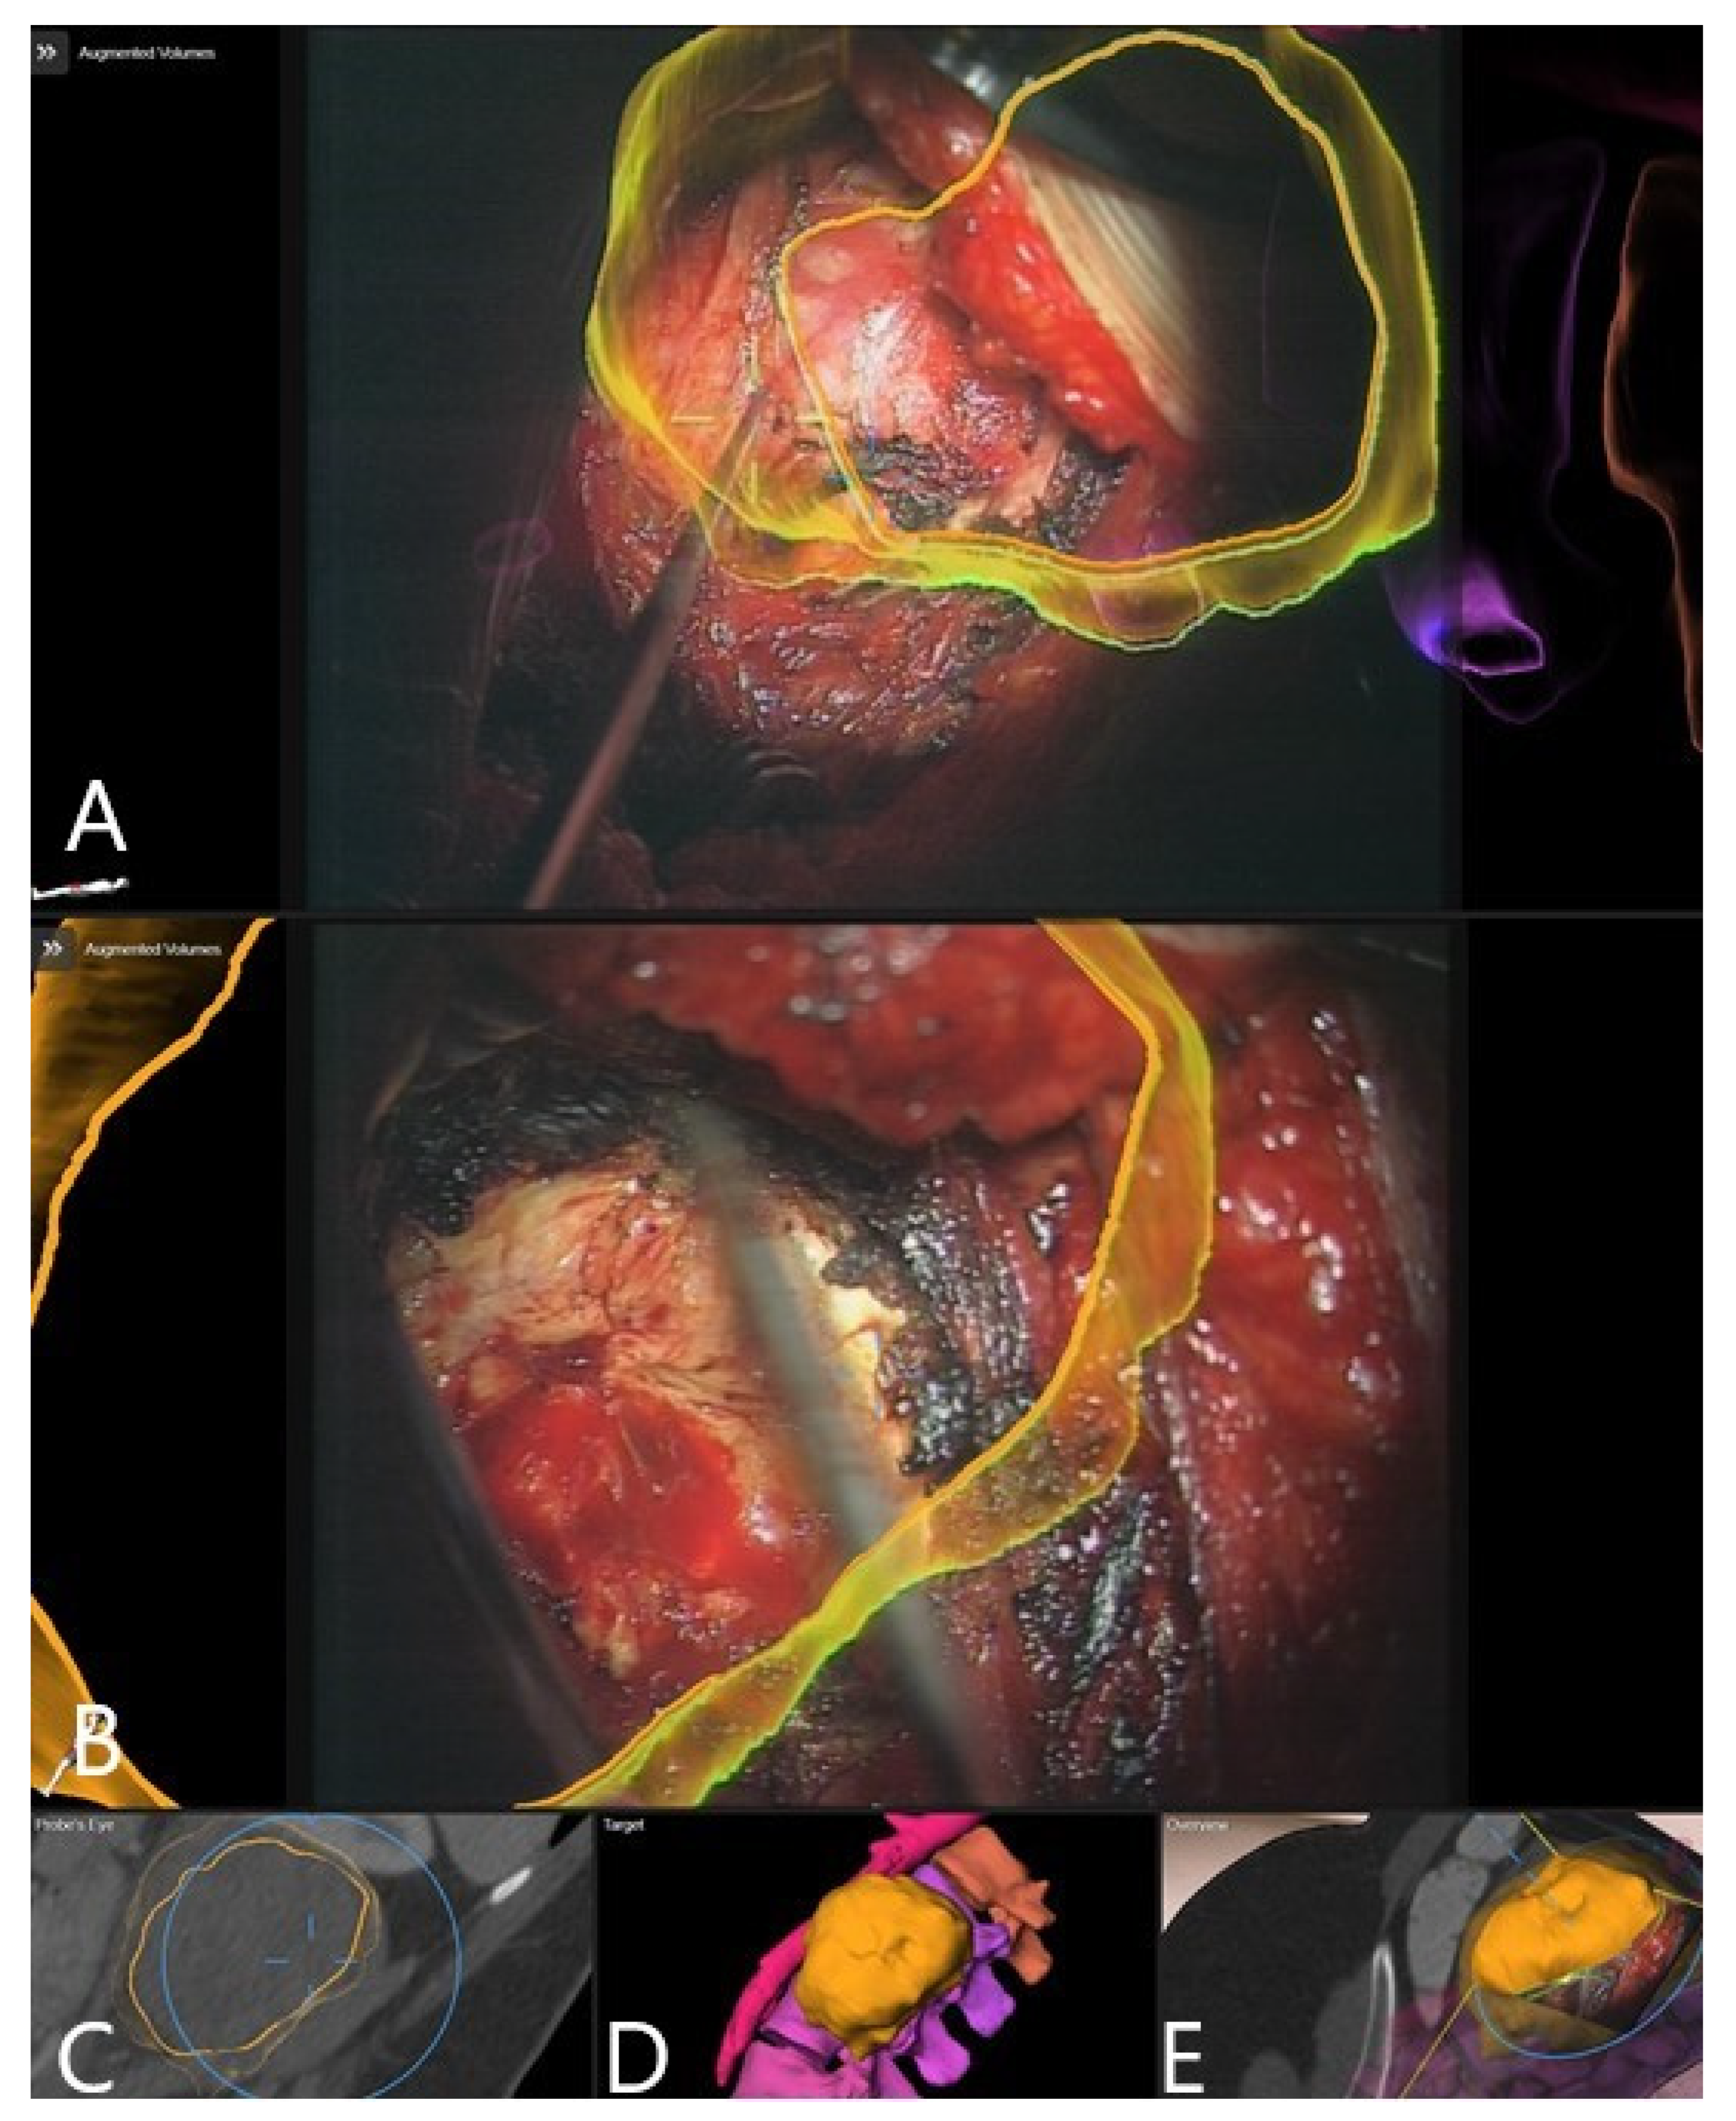

3.4. Augmented Reality

3.5. Clinical Application of iCT and AR